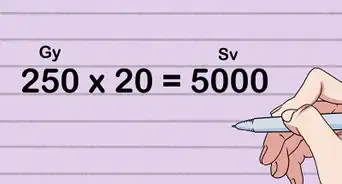

1Consult your doctor before the procedure. It is essential that you talk to your doctor before getting an X-ray, especially if you are breastfeeding or if you are or think you might be pregnant. You will be exposed to small amounts of radiation that can be dangerous for the developing fetus.[2]

- Depending on the circumstance, another imaging test might be used to avoid radiation.

- Routine X-rays are considered fairly safe but most doctors recommend waiting at least 6 months and sometimes up to a year to undergo the same routine X-ray due to radiation exposure, unless they are needed sooner (as often you may need a repeat CXR 1-2 weeks after pneumonia, or repeat films in a few weeks for fractures). If you have concerns about the risk of radiation exposure, make sure to address them with your doctor before the test.⧼thumbs_response⧽